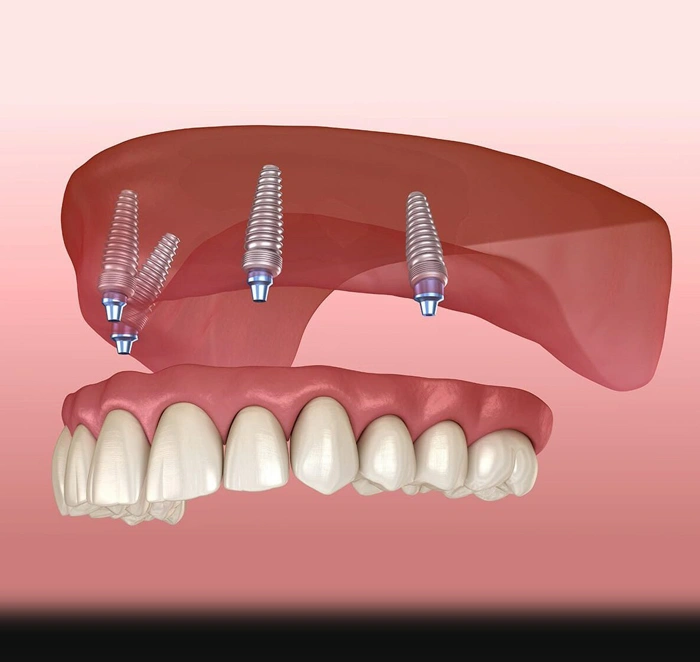

Leveraging cutting-edge design software, we merge high-resolution photographs with 3D models of your new smile, allowing you to see the transformation before treatment even begins. This digital blueprint guides the creation of 3D-printed surgical guides, ensuring each implant is placed with absolute precision according to the final intended position of your teeth. Every detail is meticulously planned to deliver a seamless, predictable, and exceptional result.

Leveraging cutting-edge design software, we merge high-resolution photographs with 3D models of your new smile, allowing you to see the transformation before treatment even begins. This digital blueprint guides the creation of 3D-printed surgical guides, ensuring each implant is placed with absolute precision according to the final intended position of your teeth. Every detail is meticulously planned to deliver a seamless, predictable, and exceptional result.